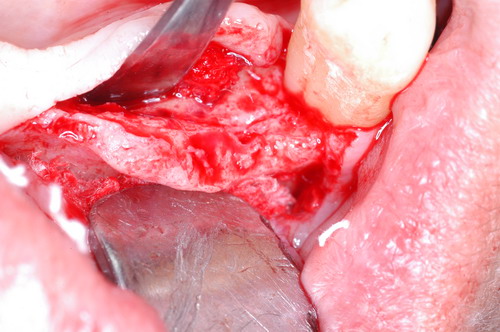

EL USO DEL ARCO GÓTICO DE GYSI , MEDIANTE UNA BÓVEDA PALATINA Y UN APOYO CENTRAL ÚNICO (BO PA YA CU) , EN LA UBICACIÓN DE LA RELACIÓN CÉNTRICA EN UN CASO DE GRAN LAXITUD TENDINOSA CAPSULAR. EL PACIENTE SE PRESENTA A CONSULTA CON UNA EDENTACIÓN PARCIAL, Y GRADO DE MOVILIDAD EXTREMO EN TODAS SUS PIEZAS REMANENTES. SE ESTUDIA EL CASO RADIOGRÁFICA Y CLÍNICAMENTE , Y EL PACIENTE RELATA ESTAR EN ESE ESTADO DESDE HACE MUCHO AÑOS. AL MANIPULAR LA MANDÍBULA EN UN INTENTO DE CONOCER EL ESTADO MUSCULAR DEL SISTEMA, SE OBSERVA UNA GRAN LABILIDAD TENDINOSA CAPSULAR QUE SE MANIFIESTA EN UNA HIPER LAXITUD EN LOS MOVIMIENTOS MANUALMENTE INDUCIDOS DE AMBOS CÓNDILOS DENTRO DE LA CAVIDAD. SE TOMAN IMPRESIONES Y SE MONTA EN UN ARTICULADOR SEMI AJUSTABLE , CORTANDO EN EL YESO LAS PIEZAS QUE SERÁN EXTIRPADAS , CONSERVANDO UNICAMENTE , AMBOS PRIMEROS PREMOLARES INFERIORES , QUE SERÁN UTILIZADOS PARA RETENER MEDIANTE RETENEDORES ELÁSTICOS LA PRÓTESIS INFERIOR , EN LA PRESUNCIÓN DE LA HIPERMOVILIDAD A QUE SERÁ SOMETIDA DADO QUE EN LA GRAN REABSORCIÓN ÓSEA , ES FRECUENTE EL ACERCAMIENTO DE TODAS LAS INSERCIONES MUSCULARES A LA PORCIÓN SUPERIOR DEL REBORDE ÓSEO , LO QUE ATENTARÁ CONTRA LA ESTABILIDAD DE DICHA PRÓTESIS PROVISIONAL. EN UNA PRIMERA SESIÓN CLÍNICO QUIRÚRGICA , SE EXODONCIA TODO EL SECTOR INCISIVO Y CANINO INFERIOR , Y AL OBSERVAR EL REMANENTE ÓSEO CANINO DE AMBOS LADOS , SE IMPLANTA EN FORMA INMEDIATA . TANSCURRIDOS DOS MESES , DONDE LA CICATRIZACIÓN ES ADECUADA , Y LA DINÁMICA MANDIBULAR ACEPTABLE , SE PROCEDE A LA ETAPA QUIRÚRGICA IMPLANTARIA MEDIANTE IMPLANTES SEMI SUMERGIDOS, CON ALGUNAS ZONAS DE REGENERCIÓN ÓSEA GUIADA FIG17 FIG18 FIG19 FIG26 DURANTE LA ETAPA DE CICATRIZACIÓN DE ESTE NUEVO ABORDAJE QUIRÚRGICO , SE ENDODONCIAN AMBOS PREMOLARES INFERIORES CONSERVADOS , LOS QUE EN UN FUTURO , CUANDO YA NO SIRVAN PARA RETENER LA PRÓTESIS REMOVIBLE PROVISORIA INFERIOR , SERÁN CORTADOS COMO RESERVA DE CAPITAL ÓSEO O BIEN COMO ELEMENTO RETENEDOR ANTE CUALQUIER TIPO DE INCIDENCIA IMPLANTARIA. ABORDAMOS LA ETAPA PRIMARIA PROTÉTICA , UNA VEZ TRANSCURRIDOS TRES MESES, MEDIANTE LA UTILIZACIÓN DE CUBETAS INDIVIDUALES , A LAS QUE REALIZAMOS UN RECORTE MUSCULAR EN BASE A STENS VERDE , COMO SI DE UNA PRÓTESIS COMPLETA SE TRATARA. DE ESE MONTAJE OBTENEMOS DOS RODETES DE METACRILATO , PERFECTAMENTE ADAPTADOS A LOS MODELOS FUNCIONALES , A LOS QUE LES OTORGAMOS LA PLANIMETRÍA DERIVADA DEL PARALELISMO CON EL PLANO DE FRANKFURT , Y UNA ALTURA (DV) QUE RESULTA DE LOS MÉTODOS MÉTRICOS DE DIMENSIÓN VERTICAL… Y QUE NOS SERVIRAN ADEMÁS DE TOMAR UNA NUEVA IMPRESIÓN FUNCIONAL MEDIANTE RECORTE MUSCULAR , PARA ADAPTAR UN DISPOSITIVO CONSISENTE EN UNA BÓVEDA PALATINA SUPERIOR , Y UN TORNILLO CENTRAL INFERIOR , LOS QUE DESPUÉS DE UN ENTRENAMIENTO ADECUADO DEL ENFERMO , NOS PERMITIRÁ REPRODUCIR EN EL BÓVEDA , EL ARCO GÓTICO DE GYSI , ENCONTRANDO DE ESTA MANERA LA OCLUSIÓN EN RELACIÓN CÉNTRICA. ACTUALMENTE ESTE MÉTODO HA SIDO RECREADO MEDIANTE LA DENOMINACIÓN DE: FIG50 FIG51 FIG52 OBTENIDO EL DIBUJO DEL ARCO GÓTICO , INSINUAMOS EN EL VÉRTICE DEL MISMO UNA PERFORACIÓN QUE FIJARÁ LA PUNTA DEL TORNILLO EN ESA POSICIÓN: RELACIÓN CÉNTICA FIG55 FIG56 FIG57 CON ESTOS PARÁMETROS SE CONSTRUYEN DOS SOBREDENTADURAS ABROCHADAS EN RÓTULAS SUPRA IMPLANTES , QUE LE OTORGAN FIJACIÓN SUFICIENTE , DANDO A LA OCLUSIÓN TODOS LOS ELEMENTOS DE UNA: OCLUSIÓN MUTUAMENTE COMPARTIDA, REFERENCIA II CON UN ESQUEMA OCLUSAL DE : FUNCIÓN DE GRUPO BILATERAL POSTERIOR DE ACCIÓN CANINA DESPUÉS DE LAS REVISIONES PERTINENTES A LA SEMANA , EL MES Y LOS SEIS MESES DE TERMINADA LA REHABILITACIÓN , SE CITA AL ENFERMO PARA UN NUEVO CONTROL AL AÑO Y MEDIO Y SE OBSERVA UNA PERFECTA SITUACIÓN TISULAR , CLINICA Y RADIOGRAFICAMENTE CONTROLADA , Y ADEMÁS LA PERMANENCIA DEL MISMO ESQUEMA OCLUSAL OTORGADO DESDE EL PRINCIPIO. SE CONTROLA RADIOGRAFICAMENTE Y SE DA EL ALTA DEFINITIVA RECOMENDANDO EL CONTROL DOS VECES AL AÑO. REFERENCIAS: I : II. : III: